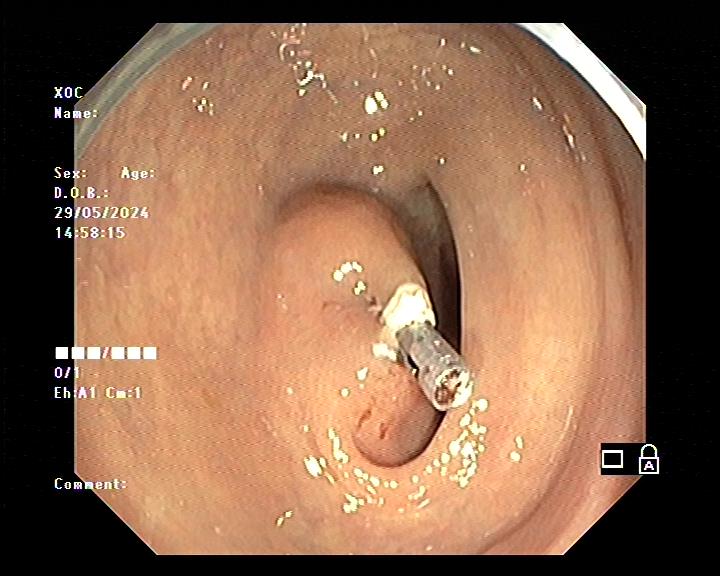

Làm gì khi phát hiện có polyp trong đại tràng? Khi phát hiện polyp đại tràng, bác sĩ có thể cắt bỏ nó và làm xét nghiệm tìm xem có tế bào ung thư hay không. Hầu hết các polyp được loại bỏ trong quá trình nội soi đại tràng.

Biến chứng có thể xảy ra khi cắt polyp đại tràng: cắt polyp đại tràng là phương pháp an toàn, rất hiếm khi xuất hiện biến chứng. Biến chứng có thể xảy ra nhưng không phổ biến bao gồm: chảy máu từ vị trí cắt và thủng đại tràng với tỉ lệ 0,1%. Chảy máu từ chỗ cắt polyp đại tràng có thể gặp ngay trong lúc cắt hoặc vài ngày sau nhưng hiện nay có nhiều thiết bị hỗ trợ cầm máu ngay trong quá trình cắt polyp. Thủng đại tràng thường cần phải phẫu thuật.